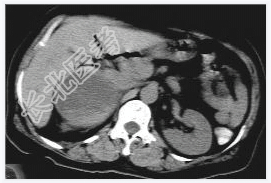

- [材料题] 女性,59岁,胸闷、头晕2天,呈持续性,伴呕吐,以进食后明显。发现“高血压”10年,“糖尿病”2年。体格检查:血压70~210/30~120mmHg。

- 简答题3、右肾上腺嗜铬细胞瘤囊变的定义是什么?

- 简答题4、右肾上腺嗜铬细胞瘤囊变的临床意义是什么?

- 简答题5、右肾上腺嗜铬细胞瘤囊变的诊断和治疗上需要注意哪些事项?